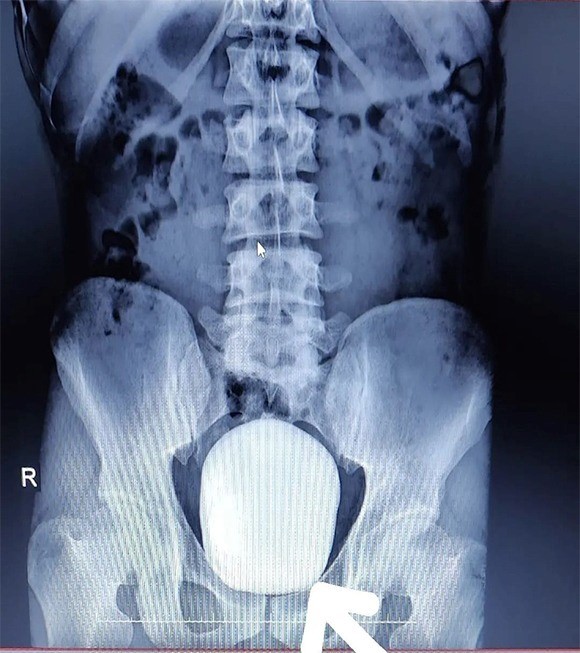

Karaman'da ikamet eden 27 yaşındaki Barış Yıldız isimli hasta idrar yaparken yanma şikayeti ile Karaman Eğitim ve Araştırma Hastanesine başvurdu. Çekilen röntgeninde hastanın mesanesinde 2 adet büyük çapta taş tespit edildi.

Doç. Dr. Güven Erbay ve Dr. Öğretim Üyesi Ahmet Şanlı tarafından yapılan cerrahi operasyonla hastanın mesanesindeki 2 taş başarılı bir şekilde alındı.

“Türkiye sınırlarında şimdiye kadar mesaneden çıkarılan en büyük taş olduğunu düşünmekteyiz” Başarılı geçen ameliyatla ilgili değerlendirmelerde bulunan Doç. Dr. Güven Erbay, “Hastanemize idrarda yanma şikayeti ile başvurdu. Yapılan tetkik ve görüntüleme sonucunda mesanesinde devasa bir taş olduğu gördük. Bunun üzerine ameliyat kararı aldık ve açık ameliyatla bu taşı aldık. Normalde mesane taşı yaşlı hastalarda ve prostatı olanlarda oluşur. Genç yaştakilerde pek beklediğimiz bir durum değildir. Başarılı geçen ameliyatın sonunda hastamızın mesanesinden 15 ve 5 santim boyutunda 2 tane taş çıkardık. Hastamızın sağlığı gayet iyi durumdadır. Şu ana kadar bilinen ve bizim de bildiğimiz kadarıyla bir hastadan çıkarılan taş bin 900 gram ağırlığındaydı. Bizim çıkardığımız 2 taşın ağırlığını ölçtüğümüzde bin 50 gram geldi. Bizim bildiğimiz üzere bu çıkarılan taşın Türkiye sınırlarında şimdiye kadar mesaneden çıkarılan en büyük taş olduğunu düşünmekteyiz" dedi.